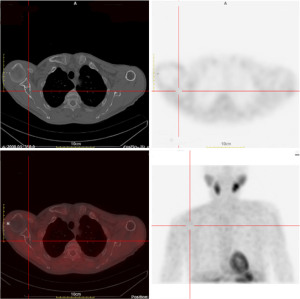

Further localization of the suspected ectopic parathyroid lesion was performed using single-photon emission computed tomography/computed tomography (SPECT/CT) with 99mTc-sestamibi parathyroid scintigraphy. No definitive uptake was noted in the typical anterior parathyroid regions. However, an ovoid, slightly hyperdense lesion was identified in the left cervical level II–III region, exhibiting patchy areas of lower density. These imaging features were highly suggestive of an ectopic parathyroid adenoma (Figure 5). Although not available in our institution at that time, 18F-fluorocholine positron emission tomography (PET)/CT has been increasingly recognized as a highly sensitive imaging modality in patients with ectopic or inconclusive parathyroid adenomas.